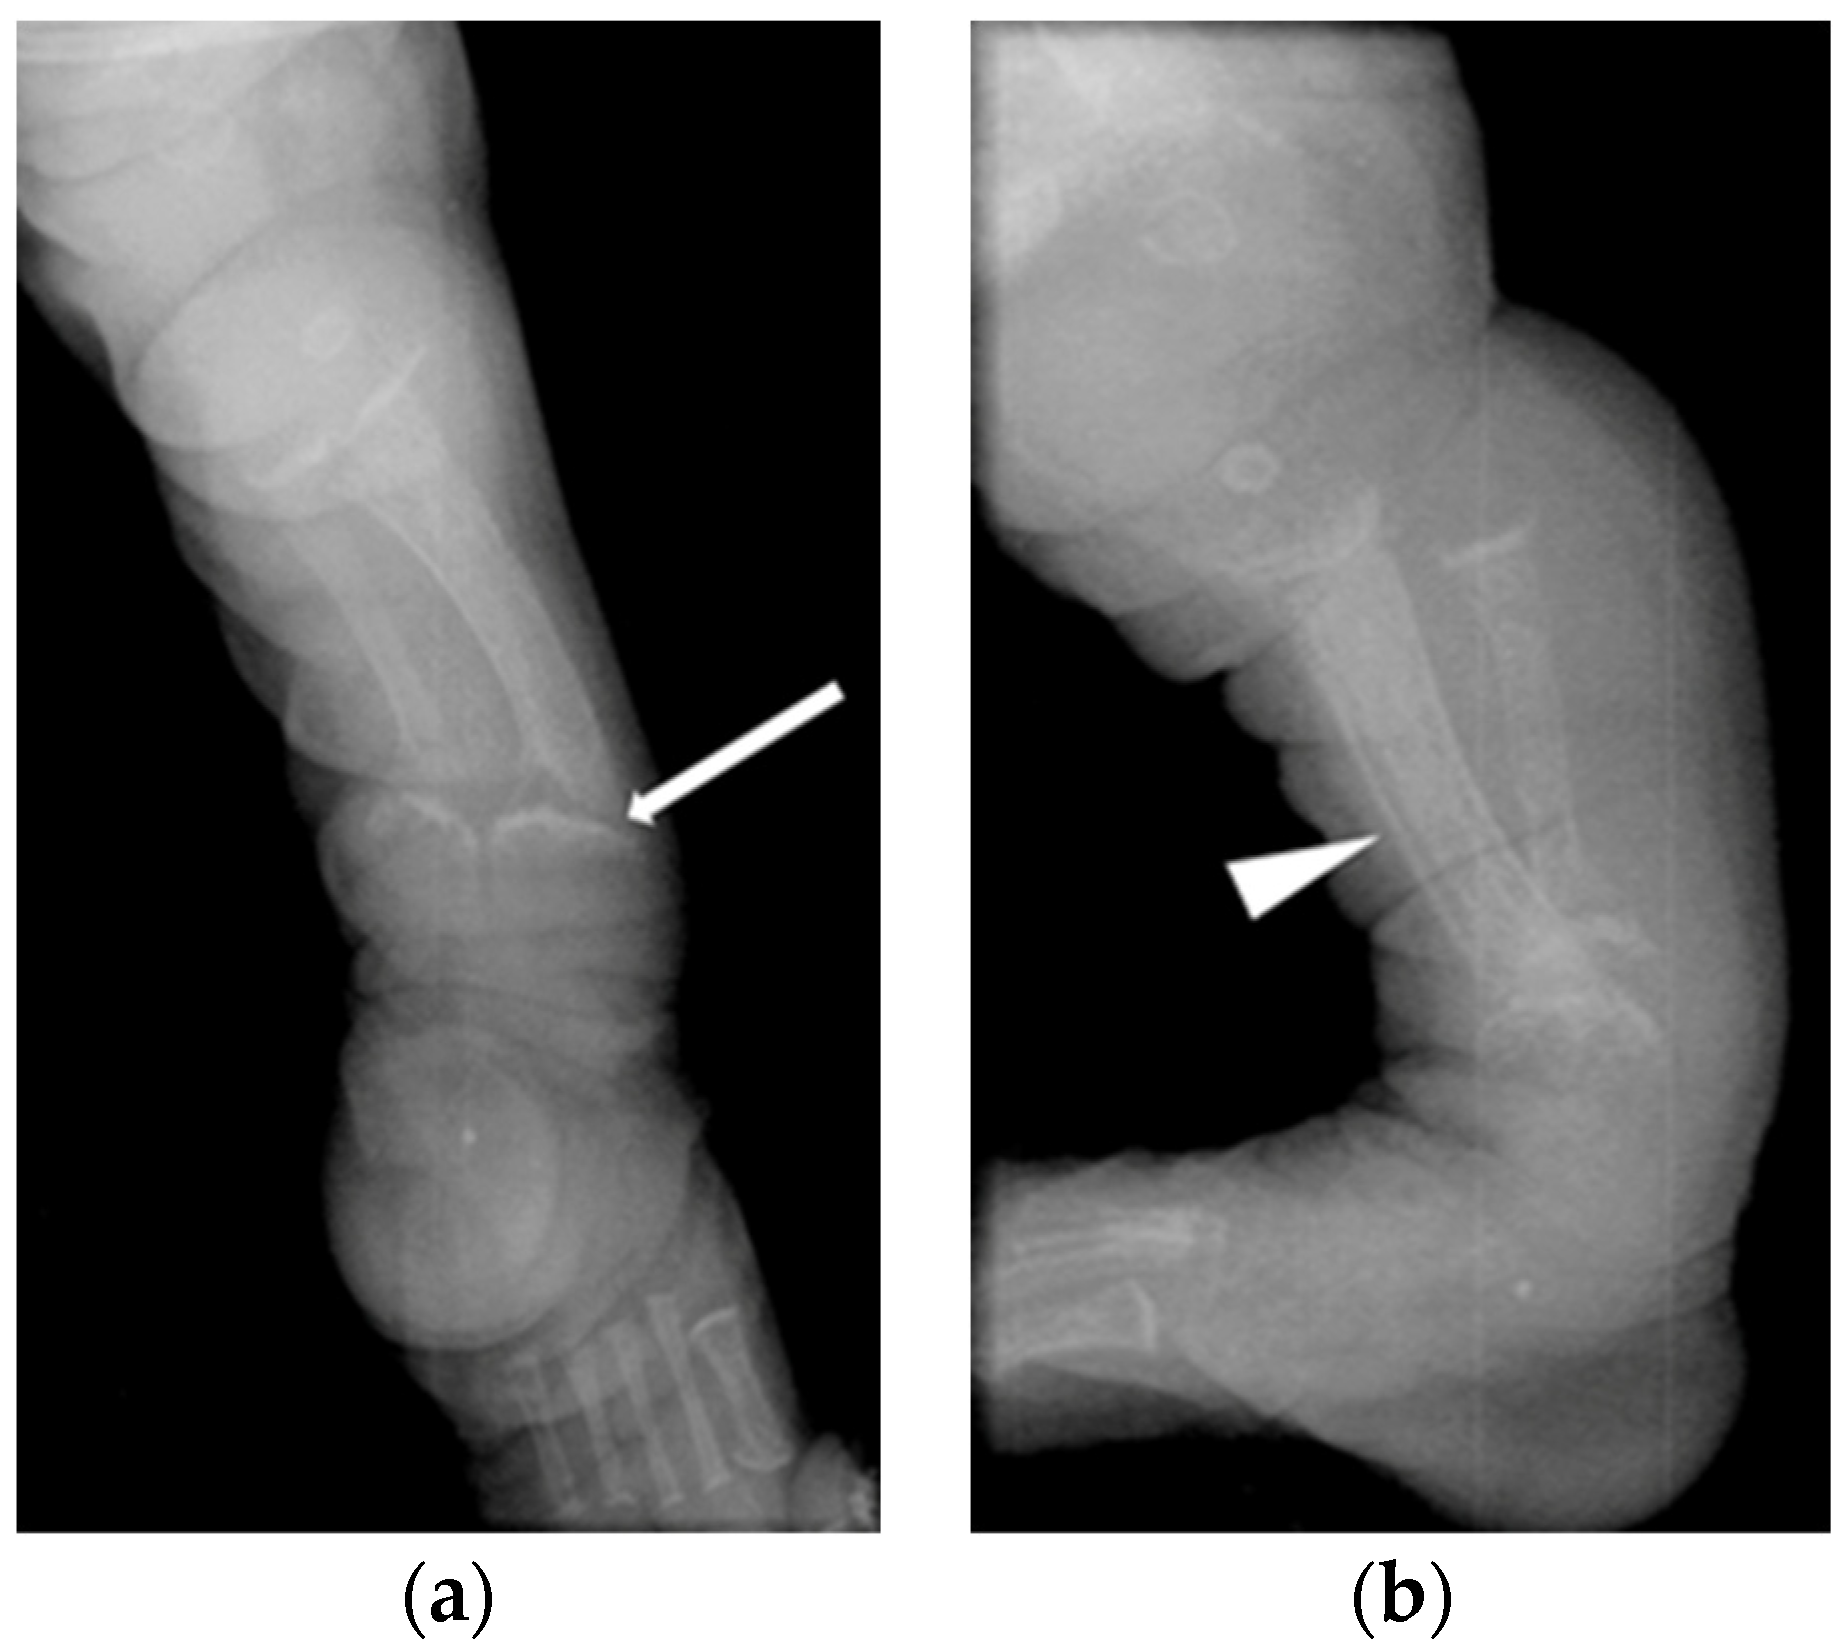

| Patient 4 | Acute fracture of the proximal left humeral neck (Figure 3a), antenatal fractures | 252 ↑ | 2.32 | 1.62 | 1007 ↑ | 121 | Vitamin D 600 IU, minimal handling for 5 month | |